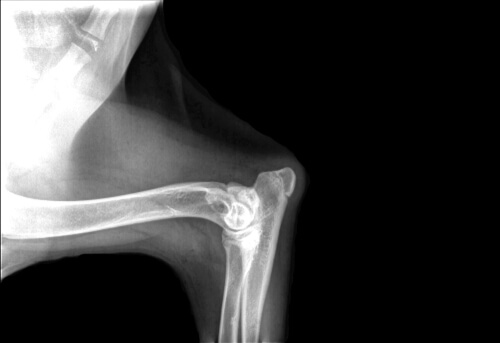

Osteocondrosis del hombro

La osteocondrosis del hombro se produce en perros en crecimiento de razas grandes y gigantes. El cartílago de la cabeza del húmero sufre una lesión llamada ‘falla’ que provoca el engrosamiento de todo el cartílago que se forma por células defectuosas que acaban muriendo. Esto causa una unión incorrecta entre el hueso y el cartílago.

La razón de esta enfermedad es multifactorial, aunque se cree que la raza y la nutrición están entre los factores claves:

- Raza.

- Edad.

- Sexo.

- Crecimiento rápido.

- Anomalías anatómicas.

- Dieta incorrecta con un exceso de nutrientes o animales sobrealimentados.

No unión de la apófisis ancónea

La no unión de la apófisis ancónea o, más comúnmente conocida como displasia de codo, consiste en un desfase del crecimiento de los huesos cúbito y radio. Esto causa que uno de los dos huesos crezca más rápido que el otro y exista una presión en la articulación del codo.

En la mayoría de los casos, para resolver el problema, se acude a la cirugía, la cual suele eliminar un fragmento del hueso y lo redirige.